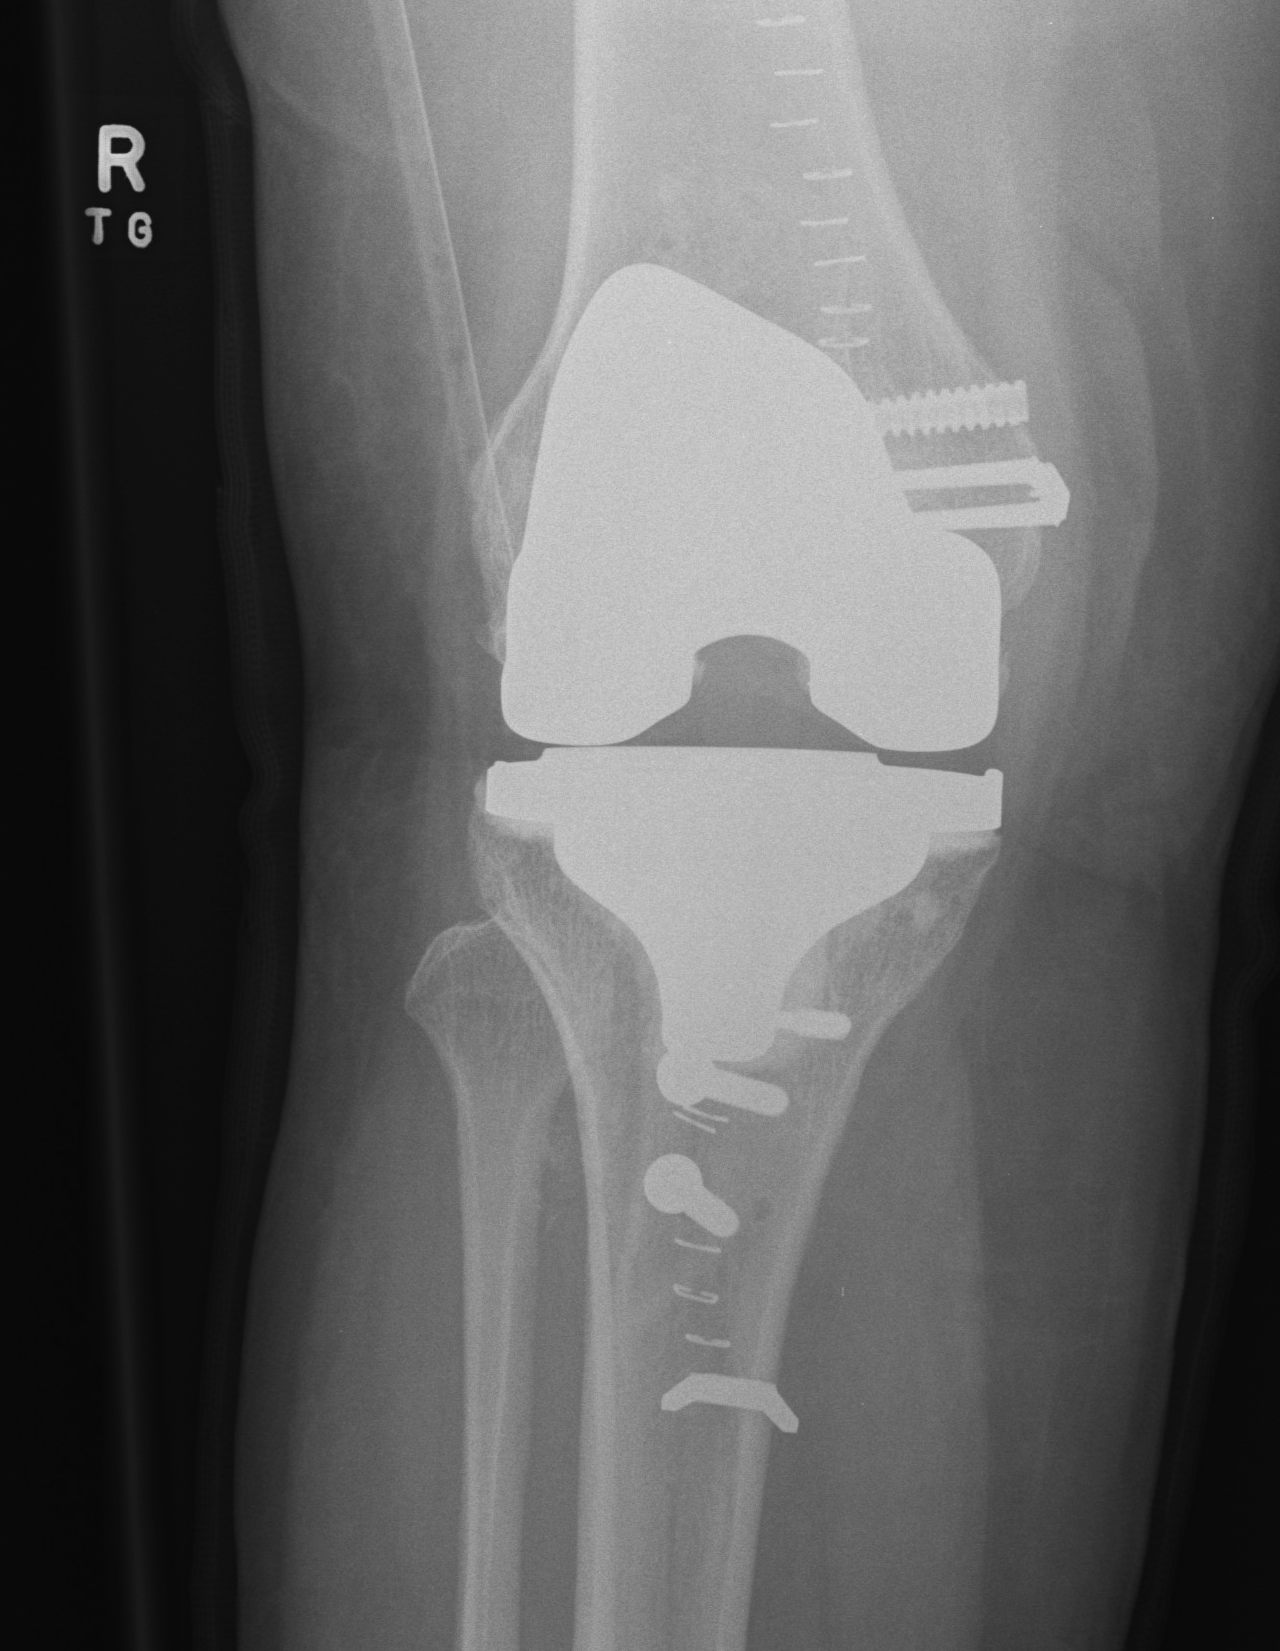

Surgical options

1. Lateral release + Patella resurfacing

2. Tibial tuberosity transfer +/- MPFL reconstruction

![]()

Barber et al Arthroscopy 2008

- 91% successul in eliminating instability in 35 knees

- used Elmslie Trillat